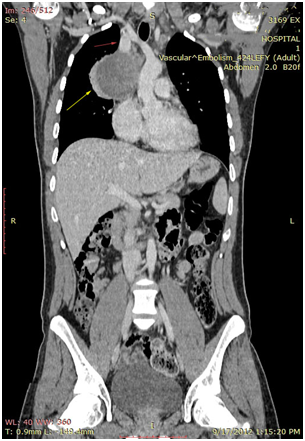

The 1st case we report is of a 22-year-old Caucasian male, who was admitted to our hospital with a 3-days history of progressive dyspnea on exertion, neck swelling, fatigue, persistent chest pain, pyrexia, and a cough that was occasionally productive of blood. The physical examination revealed a heart rate of 115 beats per minute (Sinus Rhythm), a respiratory rate of 25 breaths per minute and superficial vascular distention over the neck. Laboratory studies revealed elevated serum α-fetoprotein (AFP) (5380 IU/ml) and D-dimer (481ng/ml). A chest X-ray in the poster - anterior view, upon admission, depicted a suggestive right upper mediastinal mass (Bild 1). Radiography was followed by contrast-enhanced CT scan that revealed a large, homogeneous mediastinal mass crossing into the anterior mediastinum and compressing – encasing the superior vena cava. It also showed signs of thrombosis of the left brachiocephalic vein, and multiple filling defects at the left pulmonary artery indicating embolism. Subcarinal lymphadenopathy, as well as enlarged lymph nodes of the right hilum was present (Bild’s 2-5). On median sternotomy, a large non resectable tumor was observed involving the in nominate vein and the superior vena cava (Bild 6). Great care was taken to remove as much tumor mass as possible. To decompress the superior vena cava, we had to perform an extensive resection and reconstruction of the cephalad part of the superior vena cava using homolog pericardium.A histopathological examination of a section of the mass revealed a mixed NSGCT (embryonal yolk sac/endodermal sinus tumour), containing also elements of embryonal carcinoma (Figure 1-6).The patient was placed on cisplatin-based chemotherapy (BEP regimen: cisplatin 50mg/m2 on days 1-2, etoposide 165mg/m2 on days 1-3, bleomycin 30U on days 1, 8, and 15, every 3 weeks). Tumor markers were elevated for a-FP (214ng/mL) and normal for β-HCG. The patient completed 4 cycles of chemotherapy and the subsequent chest CT (Bild 7) revealed a partial remission of the mass (decrease>50% of the size). The a-FP was normal as well as the β-HCG. The remaining mass was inoperable so the patient was started on salvage chemotherapy with the TIP (paclitaxel, ifosfamide, ciplatin) regimen for 4 cycles. The post-chemo chest CT showed stable disease and the patient was referred to radiation oncologists for radiotherapy of the remaining tumor. Three months later af P was found elevated and the CTs revealed multiple brain metastases. Whole brain radiation was performed and the patient was placed on gemcitabine (d1 and d8 every 21 days). Two months later the neurologic status deteriorated with new brain metastases and the patient passed away (19 months after the diagnosis).

Bild 2 CT – axial plan of a large Yolk sac tumor in the anterior mediastinum invading the art. Carotis communis. White arrow pointing low attenuation foci, suggesting central necrosis.

Bild 4 CT – axial plan demonstrating a 10cm Yolk sac tumor invading the truncus pulmonalis and the vena cava superior.